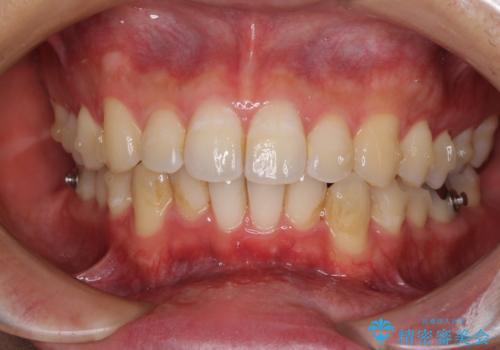

口が少し閉じにくい インビザラインによる非抜歯矯正

- インビザライン

上下顎ともにIPR(歯と歯の間を削る)と歯列全体の拡大によって口元が引っ込むように設計し、インビザラインにより治療を行うこととしました。

抜歯をして口元を下げなければならないほど出っ歯ではなかったため、少しずつ治療ゴールを変更しながら仕上げていきました。